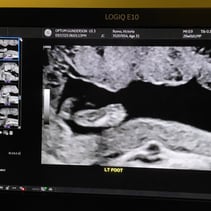

Greetings! I’ve been away from my updates for a couple of weeks, so lets get you caught up on all the things! First off, we had our Anatomy Scan today and hit the half way mark of the pregnancy. WOW. Our baby girl is doing so so well. From head to toe, she’s about 9-10inches and weighs 12oz. A week or two ago I stopped having all pregnancy symptoms besides the obvious physical changes. This was awesome but also made me a little uneasy. I also have not felt much movement and waiting 4 weeks for my 20 week appointment was starting to make me very antsy in a horribly, anxious way. Having a miscarriage the first time around has really made it difficult to relax and feel confident that everything is going well. Last week Steven went ahead and bought me a Doppler to listen to our baby’s heart beat at home while we waited for our next appointment. Once it came in and I found that wonderful sound of her heart, whew! Instant relief. Today was even better! Not only is SHE healthy, but so am I! I started going to the gym a few days out of the week and signed myself up for a 4 week Prenatal Yoga class that takes place every Saturday. My blood pressure today was 118/72 and weighing 129 which is 4 pounds more than my last appointment. I feel wonderful and even more excited than I was before to meet our girl! We’ve started clearing out the room that will be her nursery and are so grateful to the friends and family that have already started pouring their love into us and our baby with the registry gifts! Steven also surprised me with setting me up to visit family in Texas next month during my Spring Break from work. What a guy. 💕 I hope you all enjoy these photos! You‘ll see her profile with her cute little nose! There’s one of her foot, one of her crunched up with her legs bent, a crazy one of her that looks like a Halloween photo, and it’s hard to tell but one of her lips and nose. She was spinning and drinking and kissing us while she was having her first photoshoot. I will start feeling her more in the next couple of months. I have an anterior placenta so it makes things a little harder to feel since its placed in the front of my uterus. She is having fun, nonetheless. That’s all for now! We love you aaalllllll. A note from Steven: we could clearly tell during the sonogram that she gets her dance moves from her daddy.